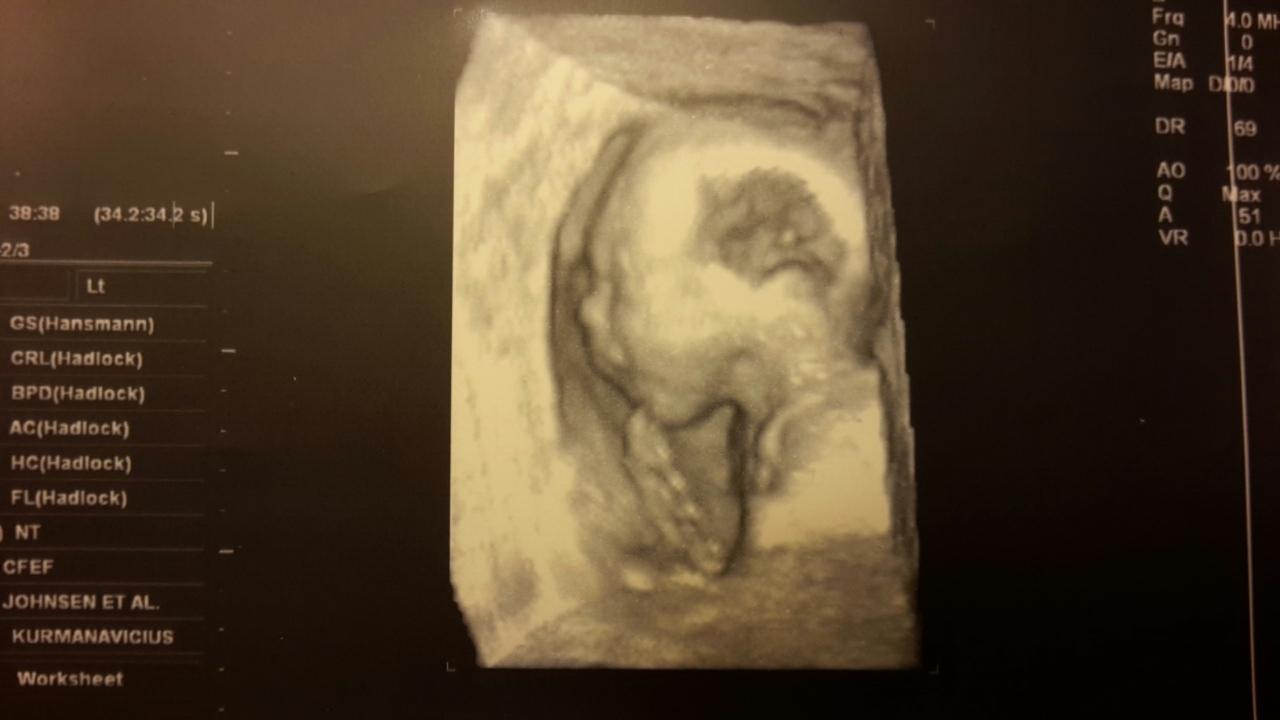

Krásné fotečky a jak ti je? 🙂